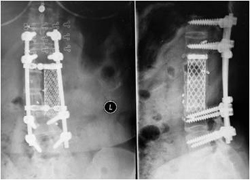

还有一个63岁的男性病人,也是因为腰背部疼痛下肢无力就诊于当地医院。检查发现T11椎体破坏。医生进行了透视下椎体肿瘤穿刺活检,但病理结果回报“正常的骨与骨髓组织,未见明显肿瘤细胞”。为了改善脊髓压迫,当地医生给病人实施了后路椎板切除及肿瘤部分切除减压和固定手术。术后病理回报为“平滑肌肉瘤”。术后半年肿瘤复发并进展。

图2-1,男性,63岁,T11椎体破坏,肿瘤累及椎管。

图2-2,术后半年MRI显示T11肿瘤复发且进展,椎管内的肿瘤对硬膜的压迫加重。